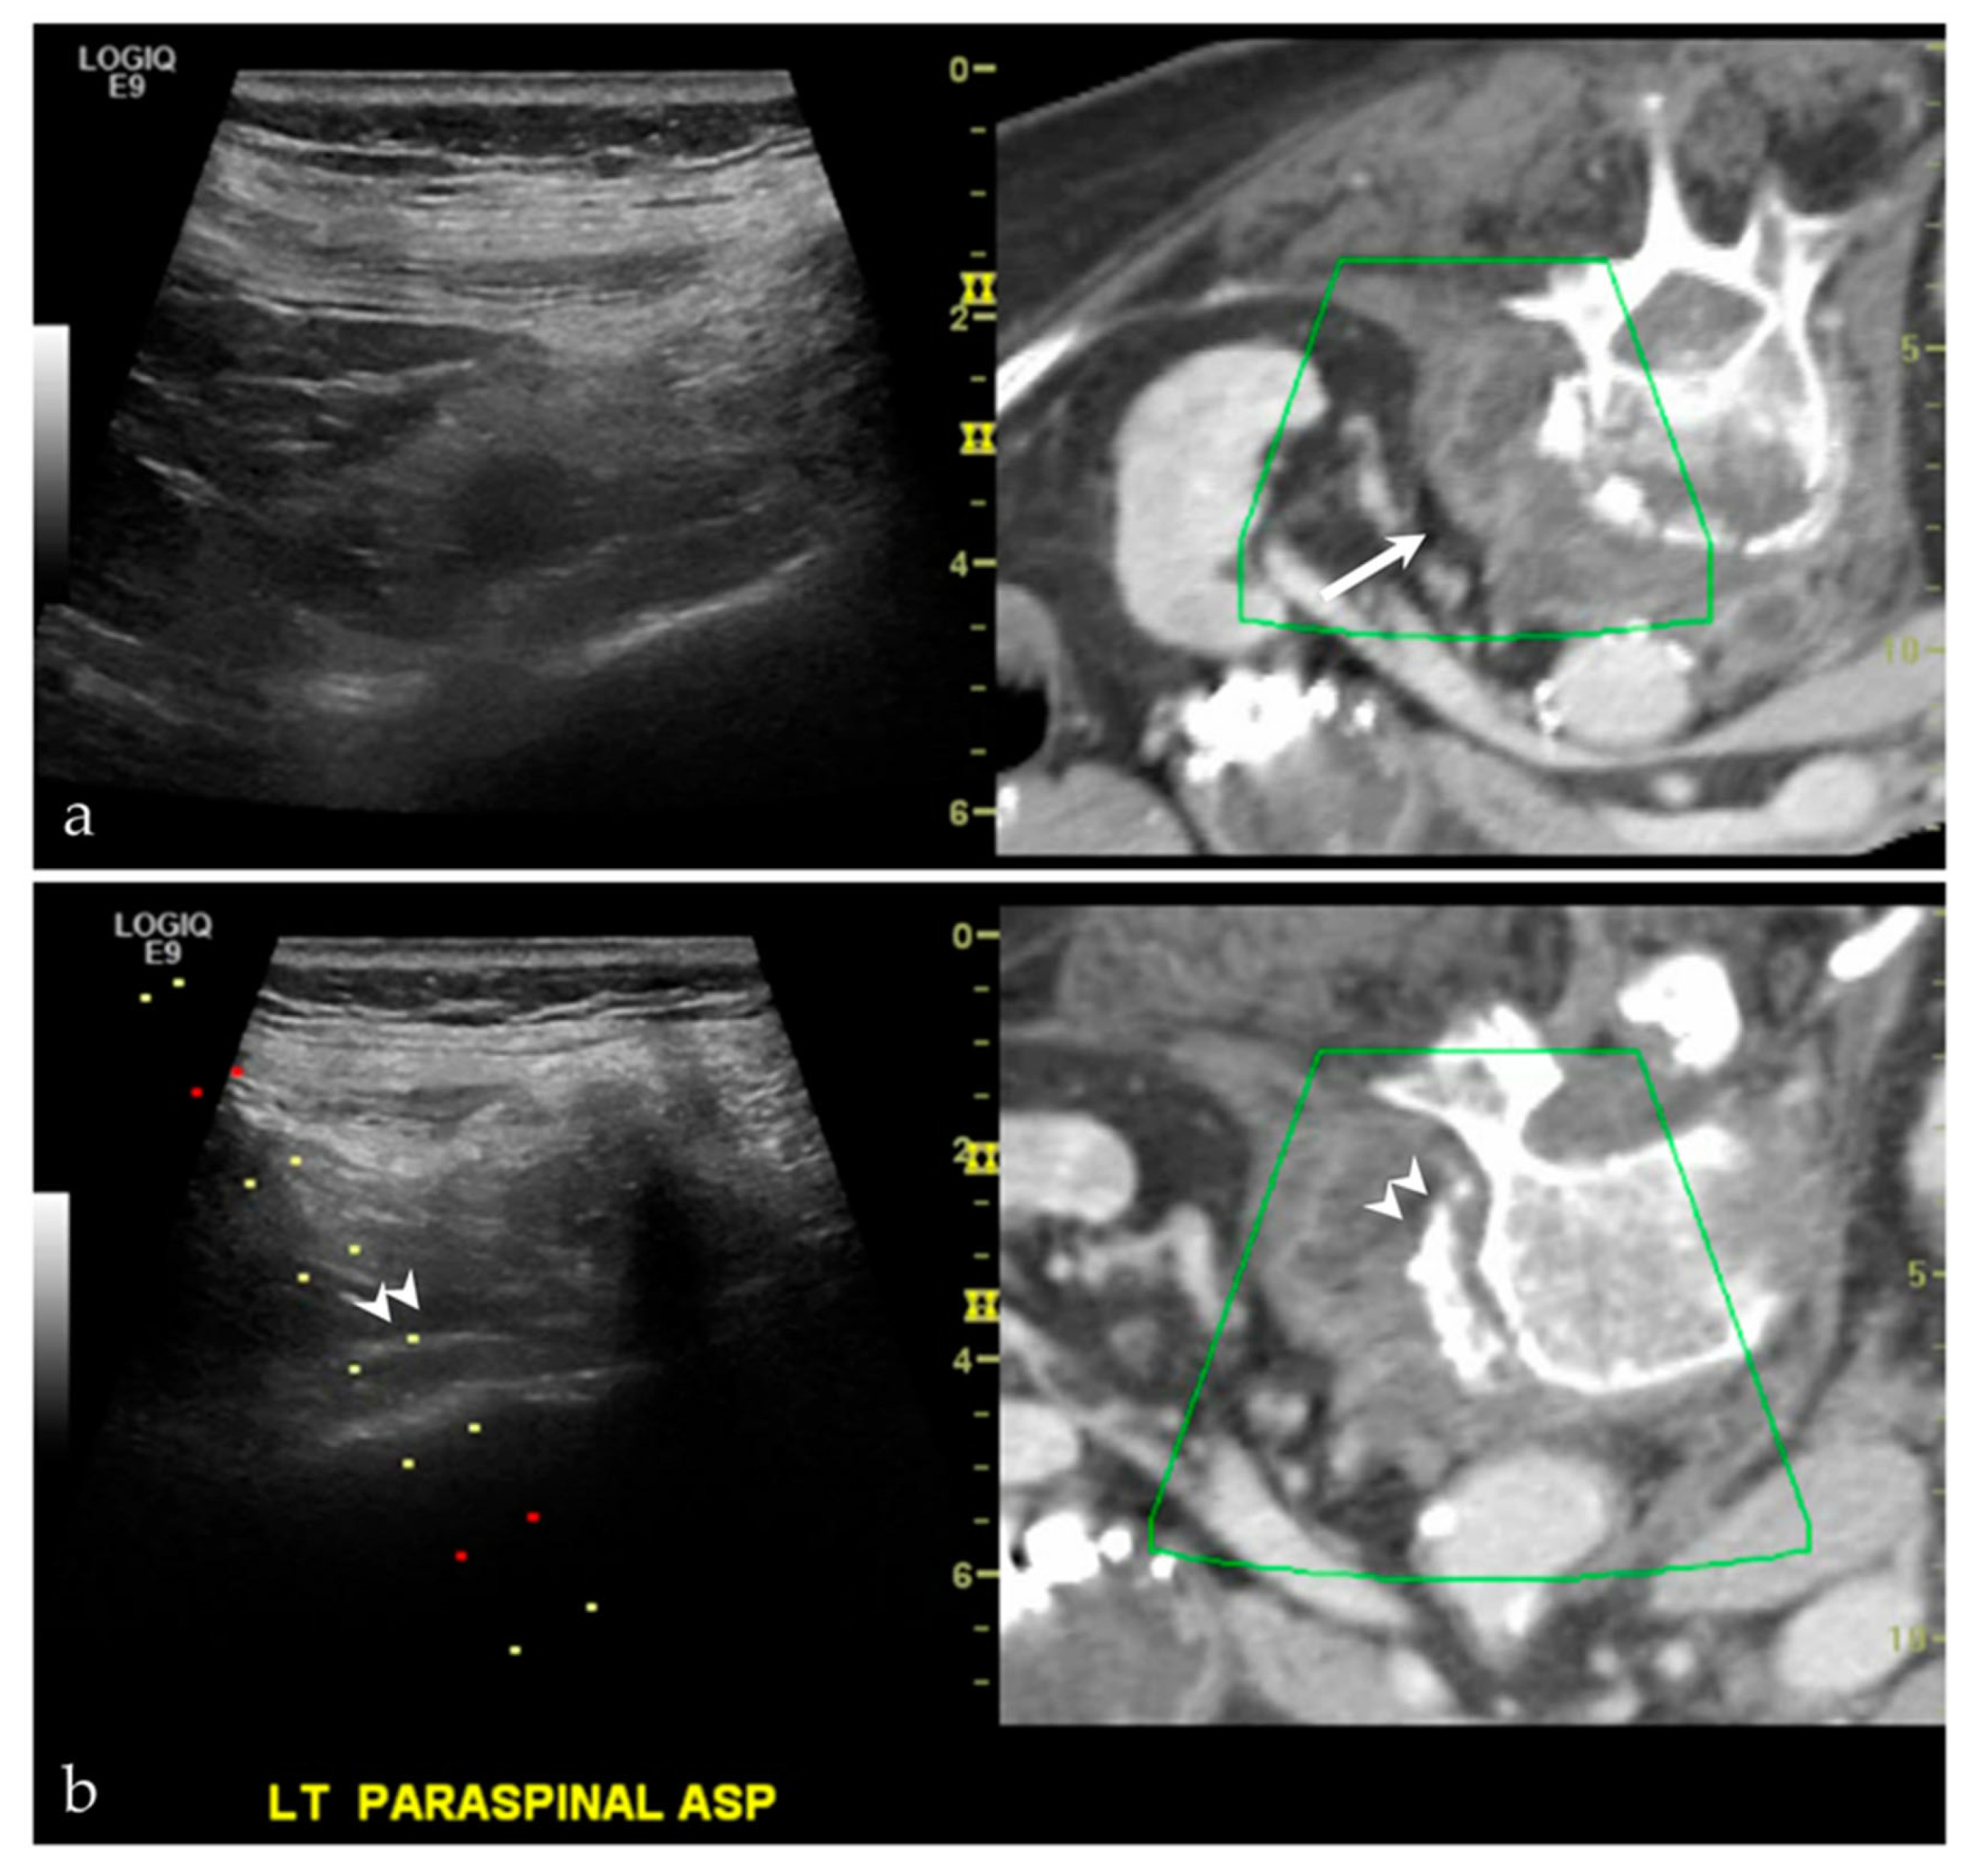

3.2.4. Targeted Percutaneous Lesion Biopsy and/or Aspiration

| NA/NA | Left paraspinal region | US-CT | Metastatic disease, unknown carcinoma | Neoplastic, malignant |